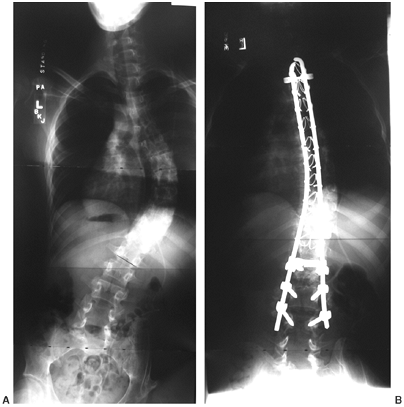

Fusion should not end in the middle of the spinal defect. Historically,

spinal fusion has been extended to the pelvis if there is fixed pelvic

obliquity greater than 15 degrees, or if the lumbosacral scoliosis is

greater than 20 degrees (Fig. 16.9). Sacral pelvic fixation can be obtained with rods placed in the first sacral foramen or with iliosacral screw fixation (190) into the pelvis by the Galveston methodology or over the ala of the sacrum (Dunn-McCarthy Technique) (191,192).

![]() |

|

Figure 16.9

Thirteen-year-old boy with thoracic level myelomeningocele and progressive curve and with pelvic obliquity. Posterior spine fusion to the pelvis stabilizes the curve and provides a level sitting platform. (Courtesy of Stuart Weinstein, MD) |